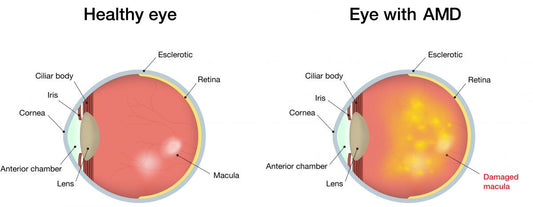

Macular degeneration (age-related)